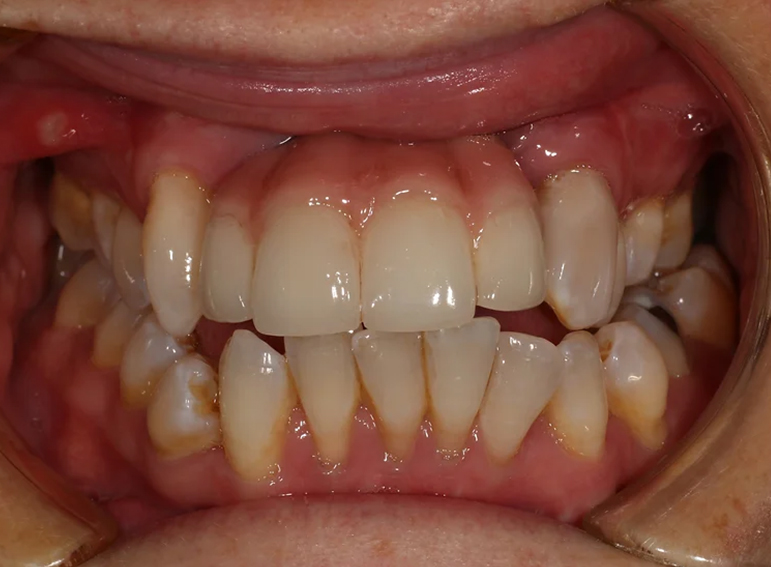

Oral rehabilitation after a road traffic accident.